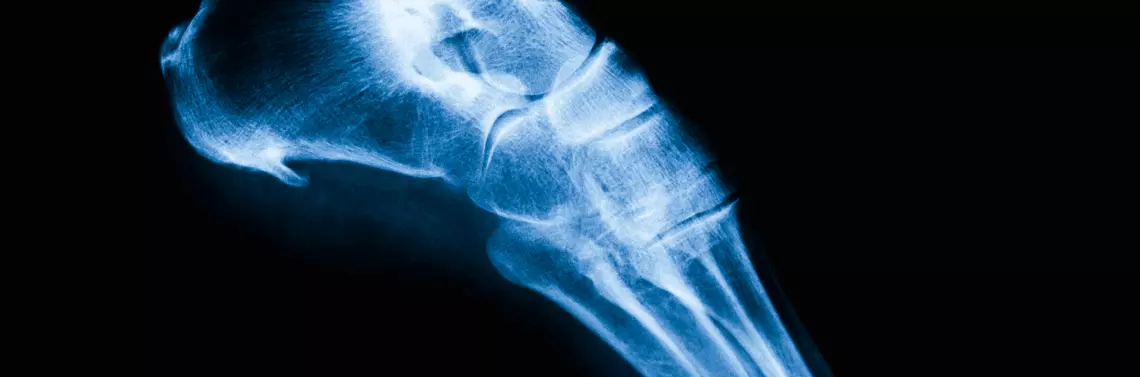

Ostroga piętowa

Ostroga piętowa powstaje na skutek przewlekłego stanu zapalnego toczącego się w okolicy rozcięgna piętowego. Jego przyczyną może być podrażnienie włókien nerwowych, przeciążenie więzadeł lub zapalenie pochewek ścięgien. W leczeniu falą ostrogi piętowej częściej wykorzystuje się falę niskoenergetyczną niż wysokoenergetyczną. Terapię ostrogi piętowej rozpoczyna się od parametrów: ciśnienie 2,5 bara, częstotliwość 10 Hz, 2000 uderzeń. Przy zwiększonej tolerancji na ból w kolejnych zabiegach dopuszczalne 2500 lub 3000 uderzeń. Terapię należy wykonywać raz w tygodniu, zaleca się 3–5 zabiegów. W przypadkach, gdy dolegliwości całkowicie nie ustąpiły, należy wykonać dodatkowych 3–5 zabiegów. Po pierwszym zabiegu następuje silne działanie analgetyczne, natomiast po drugim, trzecim zabiegu można zaobserwować przemijające przesilenie dolegliwości. U pacjentów z niskim progiem bólu skuteczna jest krioterapia poprzedzająca zabieg fali uderzeniowej, jednak zdecydowana większość pacjentów toleruje wysokie wartości ciśnienia 4,5–5 barów. Z doświadczeń Agatowskiego wynika, że zastosowanie końcówki rozpraszającej daje szybszy efekt niż zastosowanie końcówki skupiającej. Wśród 20% przypadków efektywniejsze było rozszerzenie zabiegu na całą stopę i dodanie 500 do liczby uderzeń. Leczenie falą uderzeniową ostrogi piętowej skutkuje poprawą wśród 90% pacjentów. Nawroty ostrogi obserwowane są rzadko, uśmierzenie objawów następuje po pojedynczym zabiegu [1].

Stokłosa podaje, że zabiegi na ostrogę powinny być wykonane trzykrotnie z trzytygodniową przerwą pomiędzy nimi. Liczba impulsów w jednym zabiegu jest zróżnicowana (500–4000), jednak przeważnie wartość waha się w granicach 1000–1500. Zalecana gęstość energii strumienia waha się w przedziale 0,02–0,33 mJ/mm², najczęściej osiąga 0,08 mJ/mm². Zastosowanie fali niskoenergetycznej nie wymaga znieczulenia. Zastosowanie fali o dużej energii (0,22–0,56 mJ/mm²) wymaga znieczulenia miejscowego, jednak zabieg wykonuje się tylko raz, ilość generowanej energii wynosi 1500–3800. Z analizy badań wynika, że zastosowanie fali niskoenergetycznej daje poprawę u 60% pacjentów po 12 tygodniach od zabiegu, pojedynczy zabieg falą wysokoenergetyczną daje poprawę u 50% pacjentów [3].